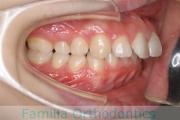

No.22V-029

- 叢生

- 上顎前突

- 19歳

- 男性

- 8448

- FEA 022

- 92万円

でこぼこを治したいということで来院されました。上下左右から親知らずも第一小臼歯も抜歯が必要で、歯科矯正アンカースクリューを併用して大臼歯を後ろに引っ張りながらの治療でした。3年弱、35回程度の通院が必要でした。

叢生が著しく、後戻りのリスクがあります。またアンカースクリューが必須のため、もしもスクリューが安定しないと、治療が難しく長くなってしまう恐れがありましたが、幸い脱落は見られませんでした。

- ≫治療後

上顎

下顎